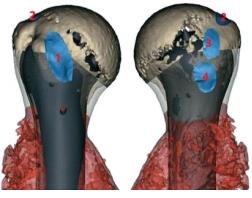

患者的三维 CT 数据被导入 Mimics V20.0 软件(Materialise Corp.,Leuven,Belgium) 以建立肿瘤和骨骼的三维虚拟模型。通过多模态图像融合技术整合CT 和 MRI 来确定肿瘤边缘。获得每例患者详细解剖学数据,包括肱骨头直径、肱骨近端和远端截骨位置、切除长度、残余肱骨的长度以及髓内腔的直径。随后评估切除边界以确定肿瘤切除和保留近端残余骨的部分,并使用 Geomagic Wrap 软件 (Geomagic inc.,Morrisville,NC) 进行手术模拟 (图 2a)。

图2 a:术前模拟 CT 和 MRI 图像融合技术建立肱骨合并肿瘤模型;b、c:基于解剖学数据的生物型多孔假体重建示意图,显示虚拟截骨范围及使用假体柄放置髓腔情况

本组 13 例随访中,均未出现半脱位或脱位的情况,甚至可以在矢状面完成环行运动,动态 X 线显示肩关节运动平稳。相比而言,有报道称患者在切除肱骨近端后,即使接受了关节置换术或植骨术,也会出现肩关节外展减少的情况 [42]。Pilliar 等 [43] 分析了来自 8 项肩关节置换术研究的 84 例患者,其MSTS 的平均得分是 70%,26% 的患者出现了机械失效。本中心研究的有利结果不仅取决于假体设计的合理性,还取决于重要的解剖结构保护和精确的手术技术。首先,肩关节和肩袖的保留直接导致了肩关节的良好功能。如果直接将残余的肩袖连接到同种异体移植物或假体上,但由于肩袖重建不当,不可避免地会发生一些近端脱位或半脱位 [44-45]。关节的保留减少了肌肉重建的难度和对肌肉嵌顿的损害,从而有利于术后恢复。其次,关节囊和肩袖的保留保持了关节的被动张力。当肩关节处于运动状态时,肩袖的被动张力在关节面之间提供了压迫应力,从而形成凹陷压缩,以稳定关节 [46]。此外,肩袖肌肉收缩的协调使各方向的压力保持平衡,有利于肩关节的稳定 [46-47]。本组 13 例均保留了肱骨头,大部分的肩袖保留完整。在截骨前,肩袖在解剖颈的每个附着点都用缝线牵引作了标记,并在假体植入后原位缝合。冈上肌完好无损,大部分冈下肌也被保留下来,因为其附着位置在截骨平面的上方。然而,部分肩胛下肌和大部分小圆肌被切除,以确保安全切缘。此外,本组使用 Marlex 补片来重建不完整的肌肉。因此,盂肱关节的稳定性得到了很好的保留,关节张力得以保持。在盂肱关节稳定的基础上,从假体表面的设计孔仔细缝合了影响肩关节外展的其它肌肉,如三角肌、胸大肌和胸小肌(图 7)。

图7 多模态重建显示肿瘤与假体位置关系及肩袖肌群附着点(1:肩胛下肌;2:冈上肌;3:冈下肌;4:小圆肌)